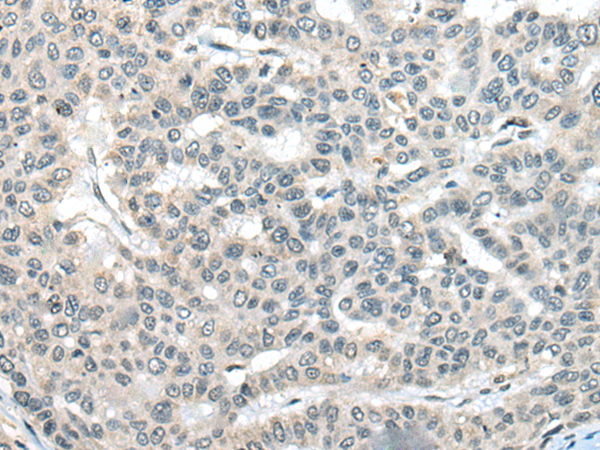

分类: 科研抗体货号: P13157别名: emb; CRM1; exp1应用: WB,IHC反应种属: Human, Mouse, Rat